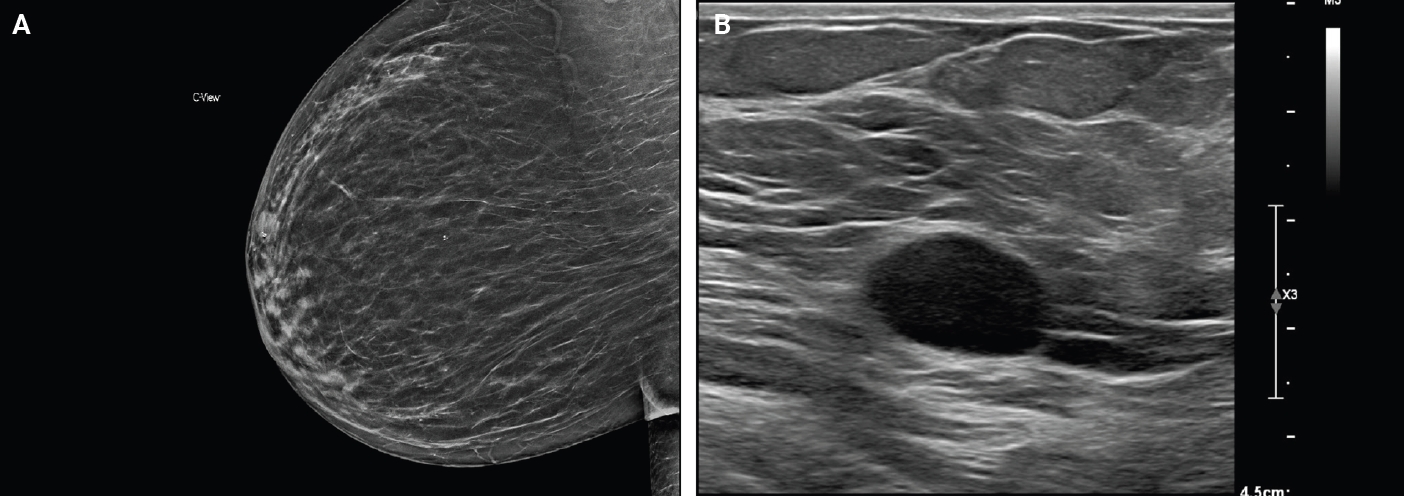

- On mammography, schwannomas present as a well-circumscribed, oval shaped, hyperdense nodule without microcalcifications (Fig. 1A). Ultrasound demonstrates a round/oval, well-circumscribed, homogenous, hypoechoic nodule with parallel orientation (Fig. 1B) [11,12]. Although not routinely performed, magnetic resonance imaging (MRI) is another modality to examine breast schwannomas. MRI T1 demonstrates a low signal and isointense nodule, while MRI T2 demonstrates a heterogeneous hyperintense signal with strong homogeneous contrast enhancement [13].

Fig. 1.Mammogram with a well-circumscribed oval mass with equal density. The arrow indicates the lesion (A). Ultrasound with an oval hypoechoic mass with well-circumscribed margins (B).